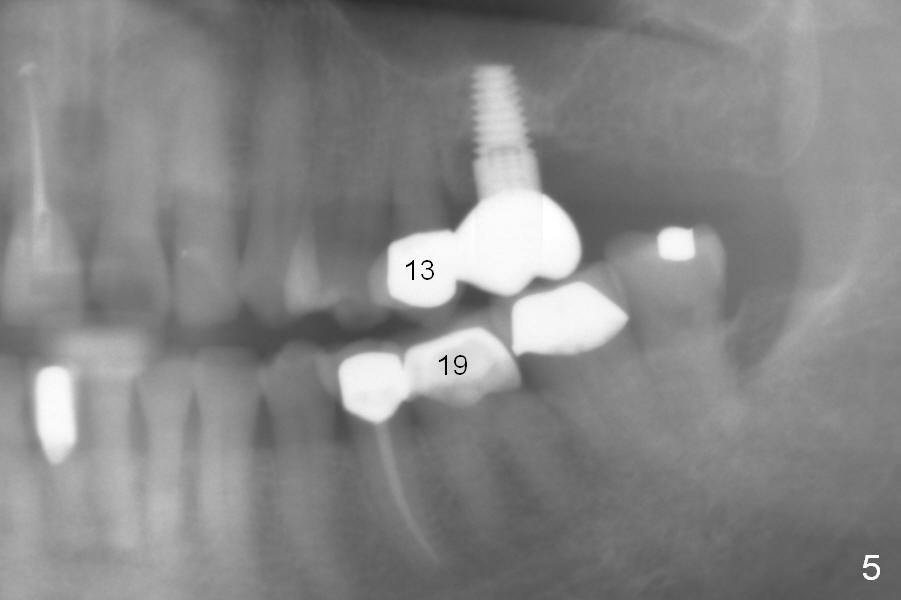

A 73-year-old woman is a possible bruxer with partial edentulism; the tooth #13 had increased periodontal ligament (pdl) space 4 years ago (Fig.1 *). A 5x14 mm tissue-level implant is placed at the site of #14 (Fig.2). The implant appears to be osteointegrated in 6 months (Fig.3). There is crestal bone loss 8 months post cementation (Fig.4 *). The persistent increased pdl at #13 is most likely associated with occlusal tramua from the tooth #19 (Fig.5 (13 months post cementation of #14)). Three years post #14 cementation, the tooth #13 has mobililty II (Fig.6); bone density increases around the apical half of the implant (arrowheads). Normally bone density is the highest coronally where functionality dictates. This indicates the bone loss is getting worse at #14 as well.